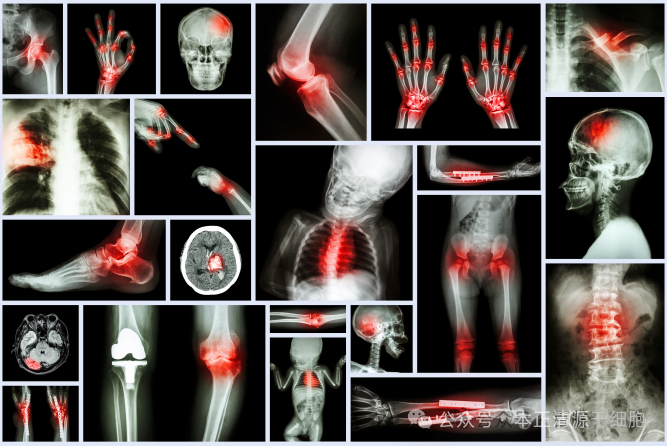

风湿性疾病是一类慢性免疫介导的疾病,涵盖类风湿关节炎、系统性红斑狼疮、强直性脊柱炎等多种疾病,严重影响患者的生活质量。传统治疗方法多以缓解症状为主,无法从根本上修复组织损伤或逆转疾病进程。近年来,间充质干细胞(MSCs)因其独特的免疫调节、抗炎和组织修复能力,成为治疗风湿性疾病的新希望。

2.类风湿关节炎(RA)

RA以关节滑膜炎和软骨破坏为特征。MSCs通过抑制炎性细胞浸润和促进软骨修复,在动物模型中显示出延缓疾病进展的效果。一项小规模临床研究对9例重症RA患者进行MSCs治疗,观察到关节肿胀和疼痛的缓解。

3.强直性脊柱炎(AS)

AS患者常表现为脊柱僵硬和骨赘形成。MSCs通过抑制Th17细胞活性和促进M2型巨噬细胞极化,减轻炎症反应。临床试验中,异体MSCs输注为传统药物无效的患者带来了疼痛减轻和活动度改善。

4.骨关节炎(OA)

OA是常见的退行性关节病,MSCs通过分化为软骨细胞和分泌营养因子,促进软骨修复。多项研究证实,关节内注射MSCs可改善疼痛和功能,但其长期疗效和标准化方案仍需探索。